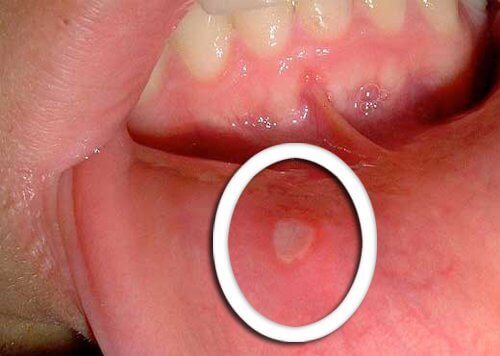

- Üst yutak kanseri ile ilgili olan erken belirtiler arasında iyileşmeyen küçük uçuklar bulunur.

- Dilin altında, diş etlerinde ya da dudaklarda kırmızı ya da beyaz uçukların (aft) oluşması tipik özelliğidir.

- Bir kaç günde geçmeyen sıra dışı değişimlere dikkat edin ve onları doktorunuza gösterin.